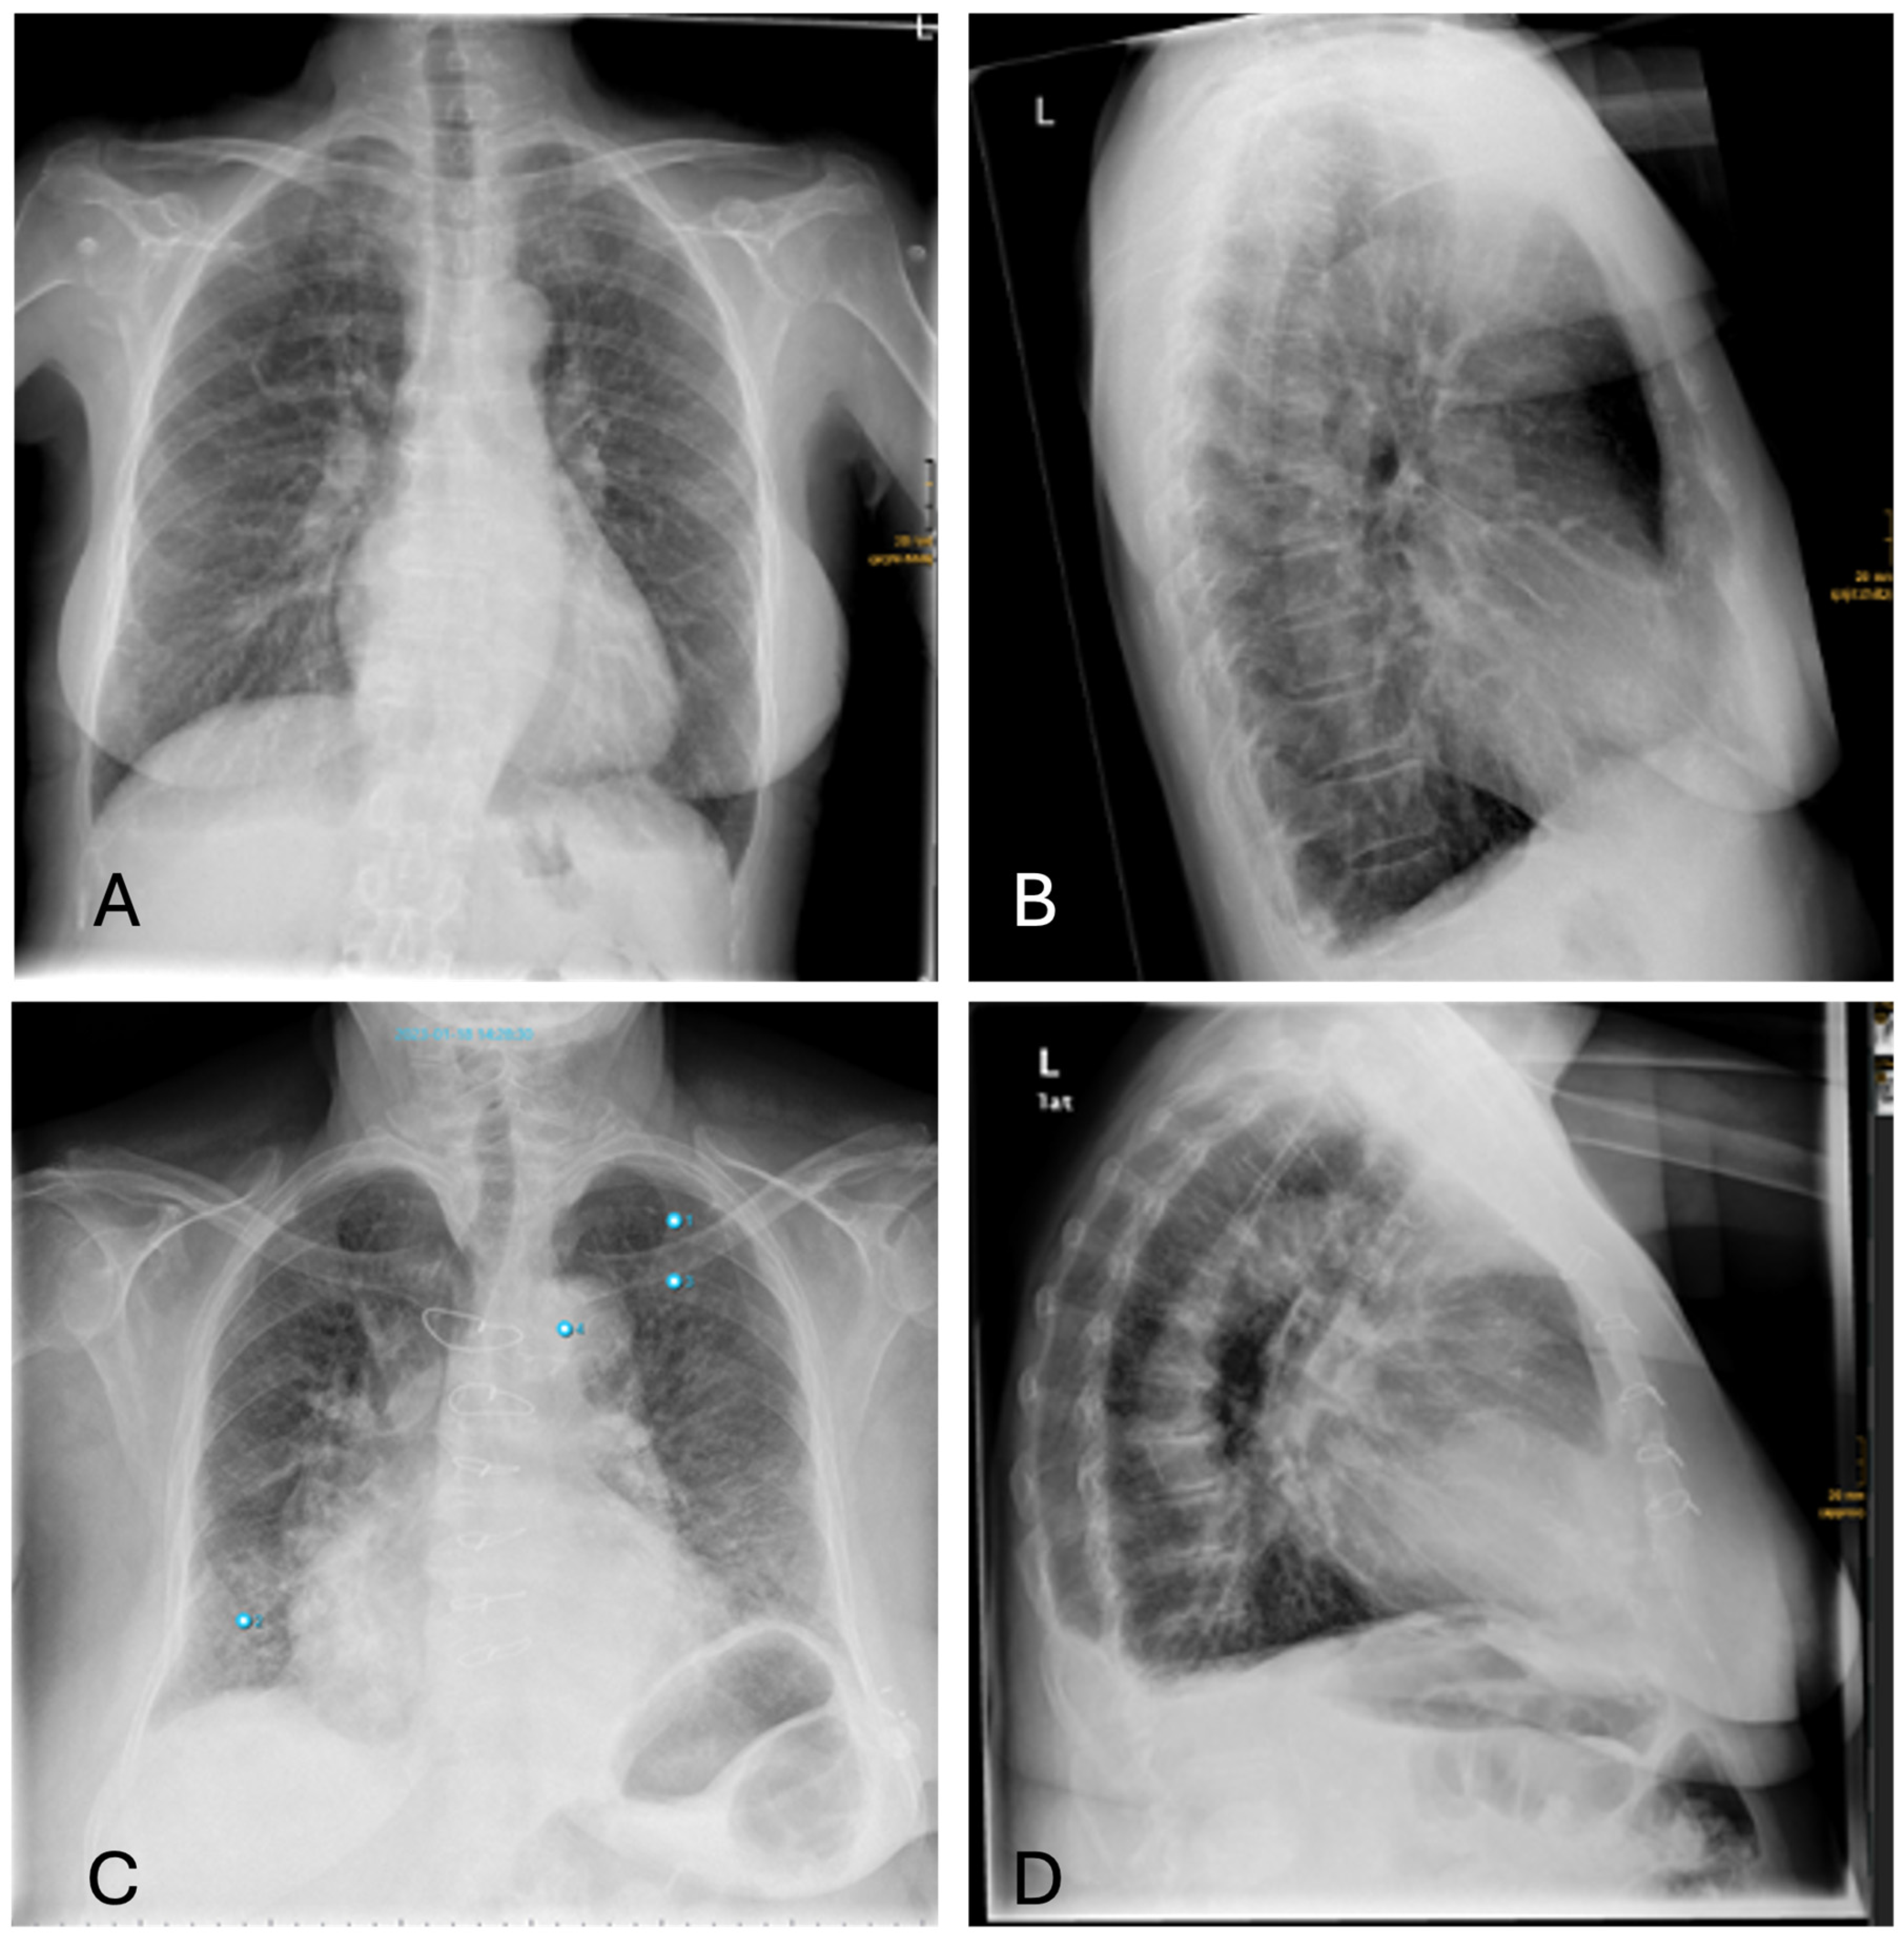

3.4.4. Pleural Effusions

Differences in the diagnosis of pleural effusion can be explained as follows: Small amounts of a pleural effusion are best identified as a dorsal costophrenic angle effusion in the lateral projection. However, AI primarily uses the PA projection for diagnosis, which means that smaller amounts of effusion might be overlooked (Figure 8).

Figure 8. Inconsistencies of pleural effusion diagnoses: (A,B)—AI missing the sulcal effusion described by the radiologist based on the lateral projection; (C,D)—Similar case with an even more prominent pleural effusion not detected by AI (Note: other findings incorrectly labelling “aortic abnormality”, “pneumonia” and “rib fracture”).